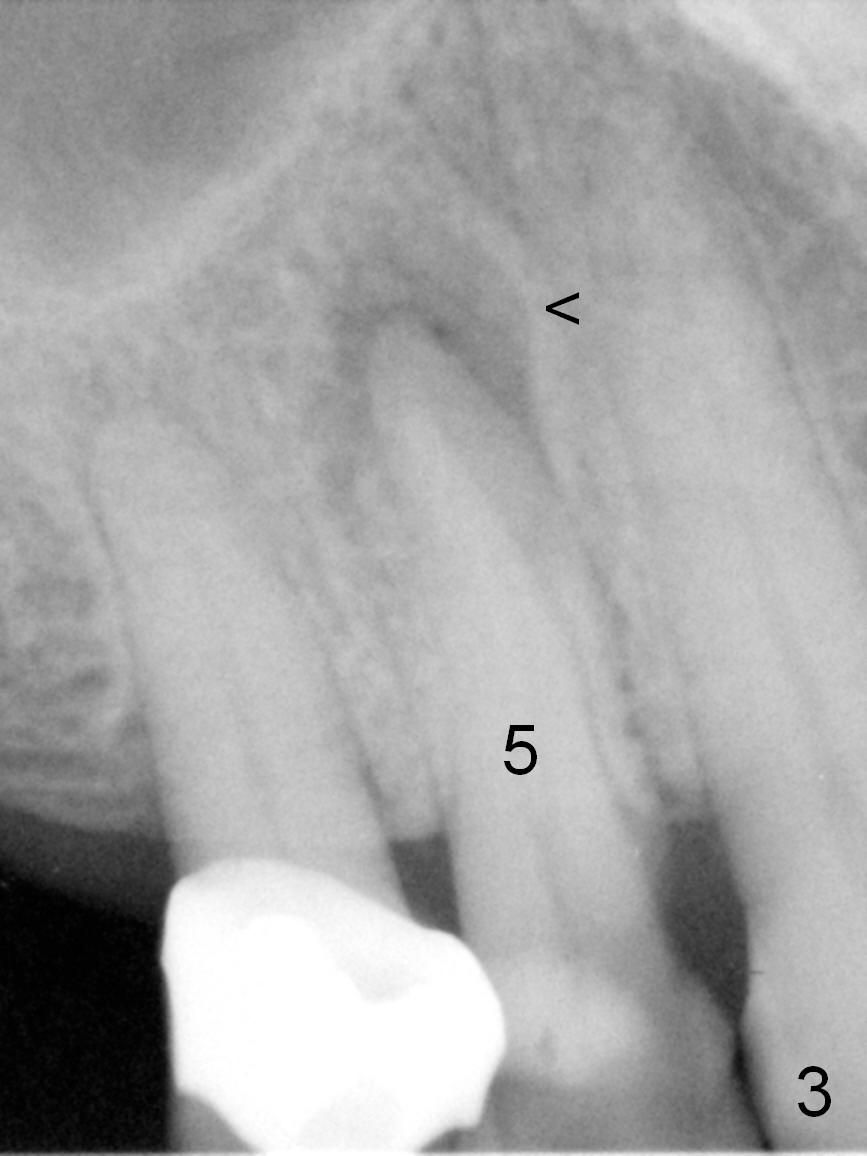

A 72-year-old lady is a bruxer with palatal subgingival fracture of the upper right 1st premolar (Fig.1) with a fistula/periapical radiolucency (Fig.2,3 <). She insists on saving the tooth, since it is asymptomatic. Bruxism must be severe, as the canine (Fig.2 ^) is shorter than the lateral incisor. She has history of #8 fracture and loosening of implant crown at #14.